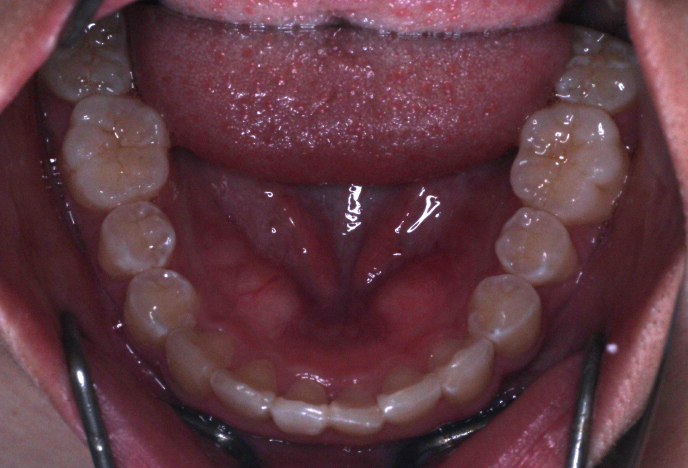

カリエールモーションが終わった時の口腔内写真です。

上の奥歯が後ろに下がったおかげで前歯には隙間ができています。

左の噛み合わせを見ると下の歯と歯の間に上の歯が入り込んでいることがわかります。

1歯対2歯の関係です。

右の噛み合わせを見ると左の噛み合わせより少し多めに奥歯を後ろに下げていることがわかります。

オーバーコレクションといって少し戻ることを想定して多めに動かしておくことを言います。